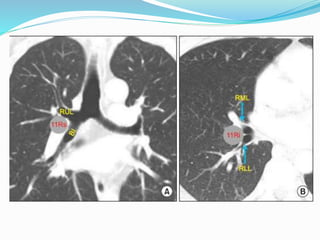

Peripheral Zone

 Station 12 : Node adjacent to lobar bronchi

 Station 13 : Node adjacent to segmental bronchi

 Station 14 : Node adjacent to subsegmental bronchi

Peripheral Zone  Station12 : Node adjacent to lobar bronchi  Station 13 : Node adjacent to segmental bronchi  Station 14 : Node adjacent to subsegmental bronchi